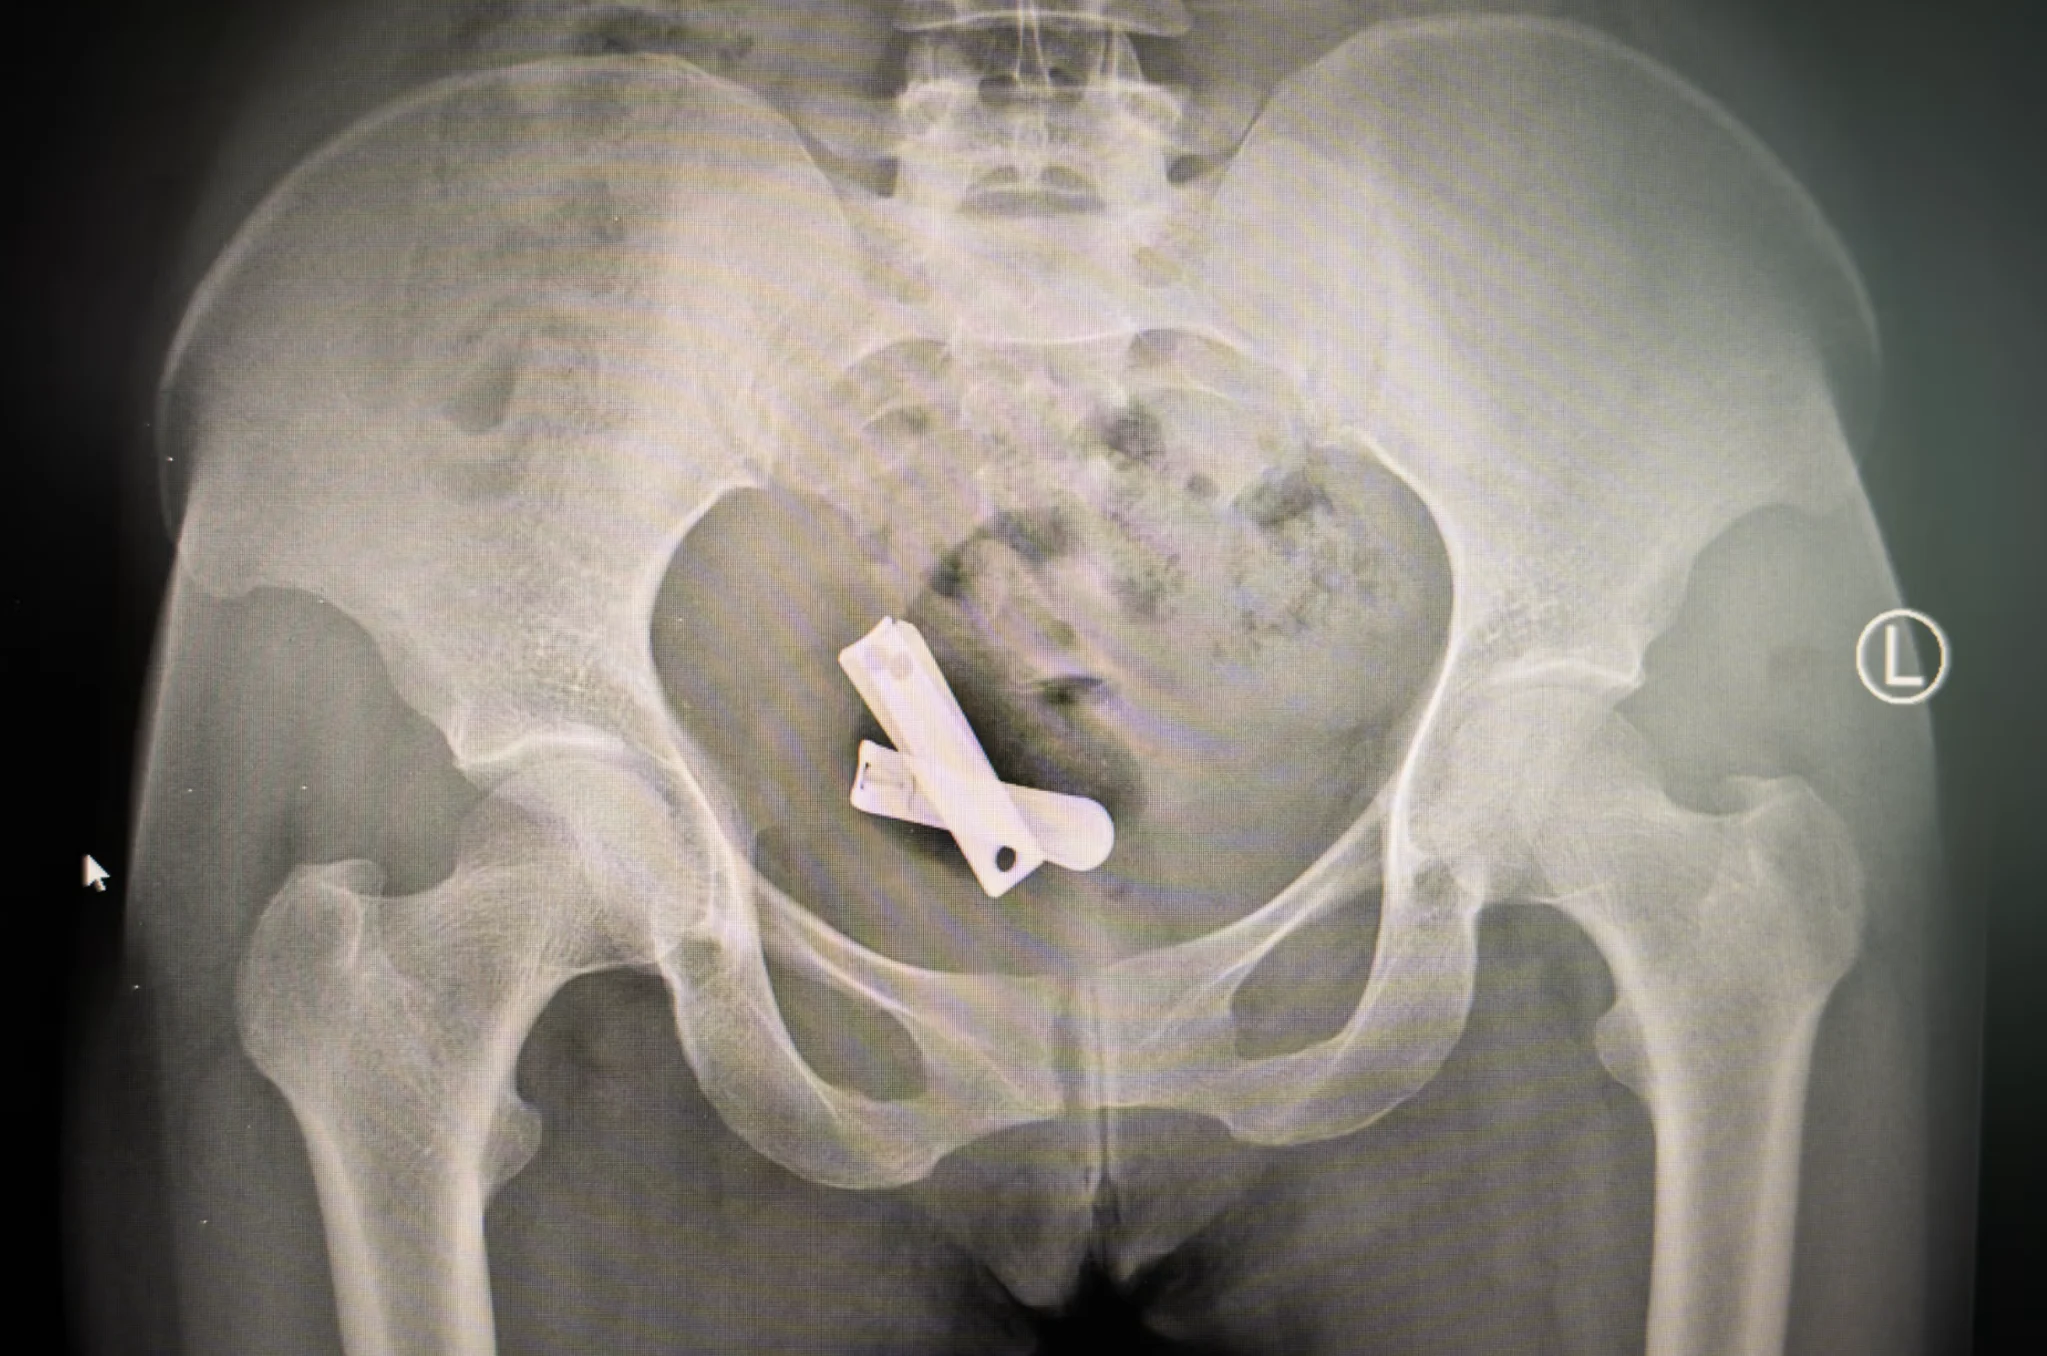

| Deze röntgenfoto laat nagelknippers zien in de baarmoeder van een vrouw. “Om hoeveel vrouwen het gaat, is niet bekend”, vertelt de Tigrese Birhan Mezgbo. Ze sprak tientallen meisjes en vrouwen over hun verkrachting en schreef er een boek over. Velen overleven de verminking niet. (Foto: Ximena Borrazás) Ons Bennekom & Beekdal Goede Doel 2024: ‘De slachtoffers van de oorlog in Tigray’ met hulp aan vrouwen, meisjes en kinderen die in de oorlog slachtoffer zijn geworden van seksueel geweld. |

NOS 26 juli 2025 In de Ethiopische regio Tigray is het nu officieel 2,5 jaar vrede, maar veel vrouwen dragen de pijn uit de oorlog letterlijk in zich. Zij werden het slachtoffer van gruwelijk seksueel geweld door Ethiopische en Eritrese soldaten, die objecten in hun baarmoeders duwden met als doel ze onvruchtbaar te maken. Van roestige schroeven tot nagelknippers en handgeschreven briefjes gewikkeld in plastic.